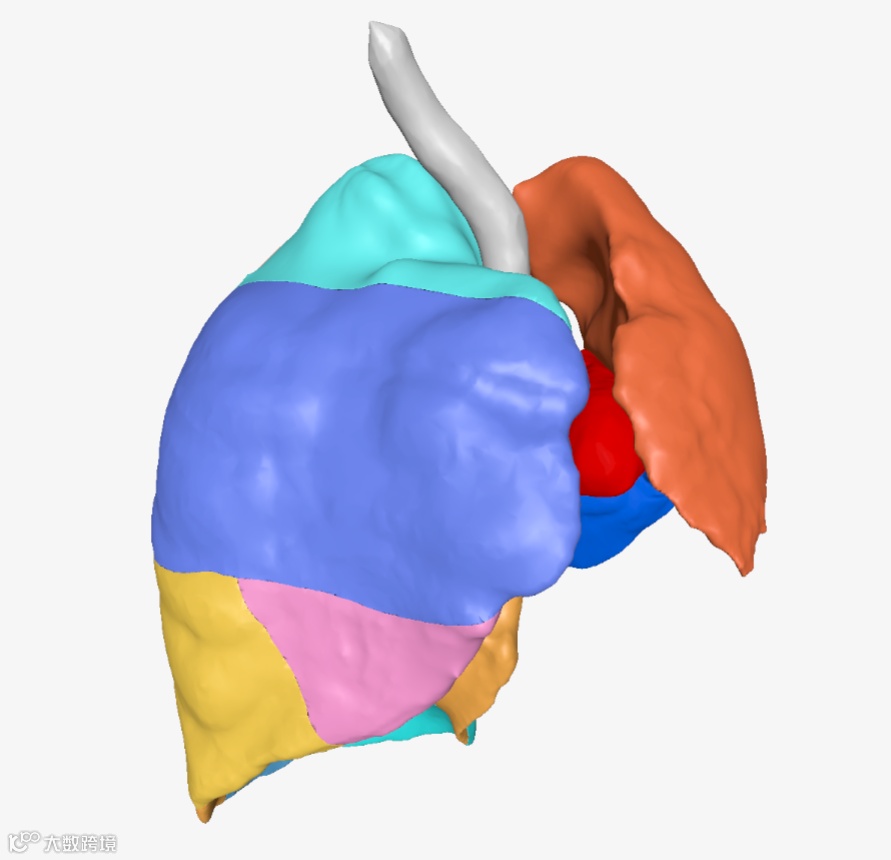

▲▲▲三维重建肺叶肺段

智能识别术后缺失的左肺肺段 -

对发生形态学代偿的右肺肺段进行精确分割 -

对右肺上叶前段实性结节的准确定位